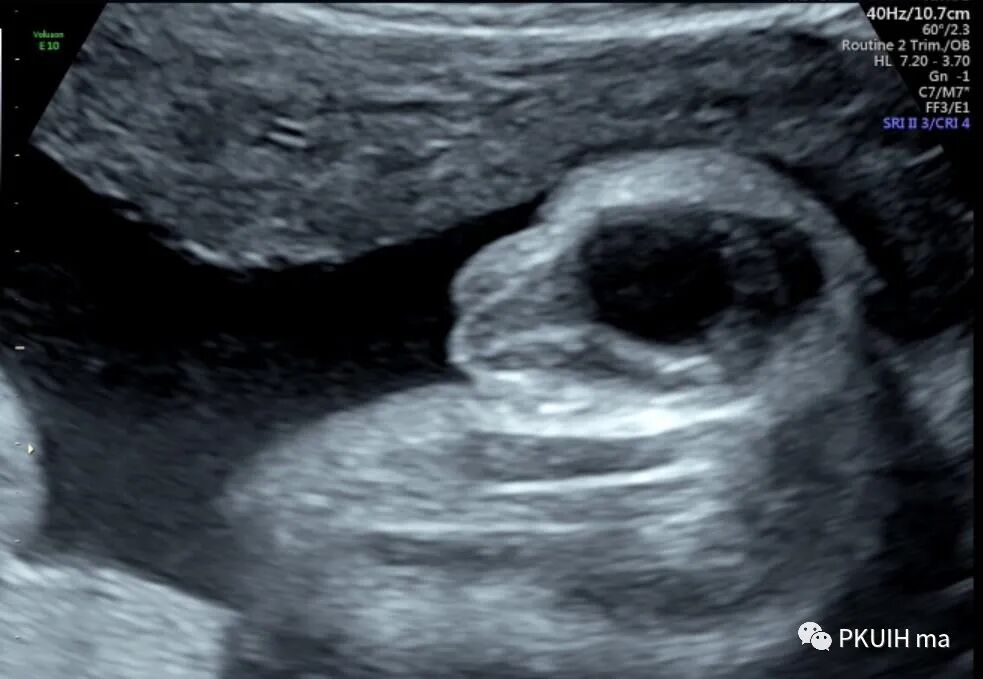

超声显示外生殖器为女性特征,肛门前方见囊性回声,冠状切面显示囊性回声延至会阴处

囊性回声似呈葫芦状,下方大,上方小